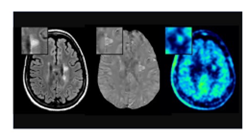

Our research spans neuroscience, immunology, genetics, and advanced imaging, including efforts to better visualize axons and myelin and to develop regenerative strategies for MS.

Experiencing a sudden change in symptoms can be unsettling, but it’s important to know that not every worsening of symptoms represents a true MS relapse. A true relapse reflects new inflammatory activity in the central nervous system and causes new neurologic symptoms or a clear worsening of previous ones that persist for at least 24–48 hours, without another explanation such as infection or fever. These relapses often correspond with new lesions seen on MRI and may sometimes require treatment...